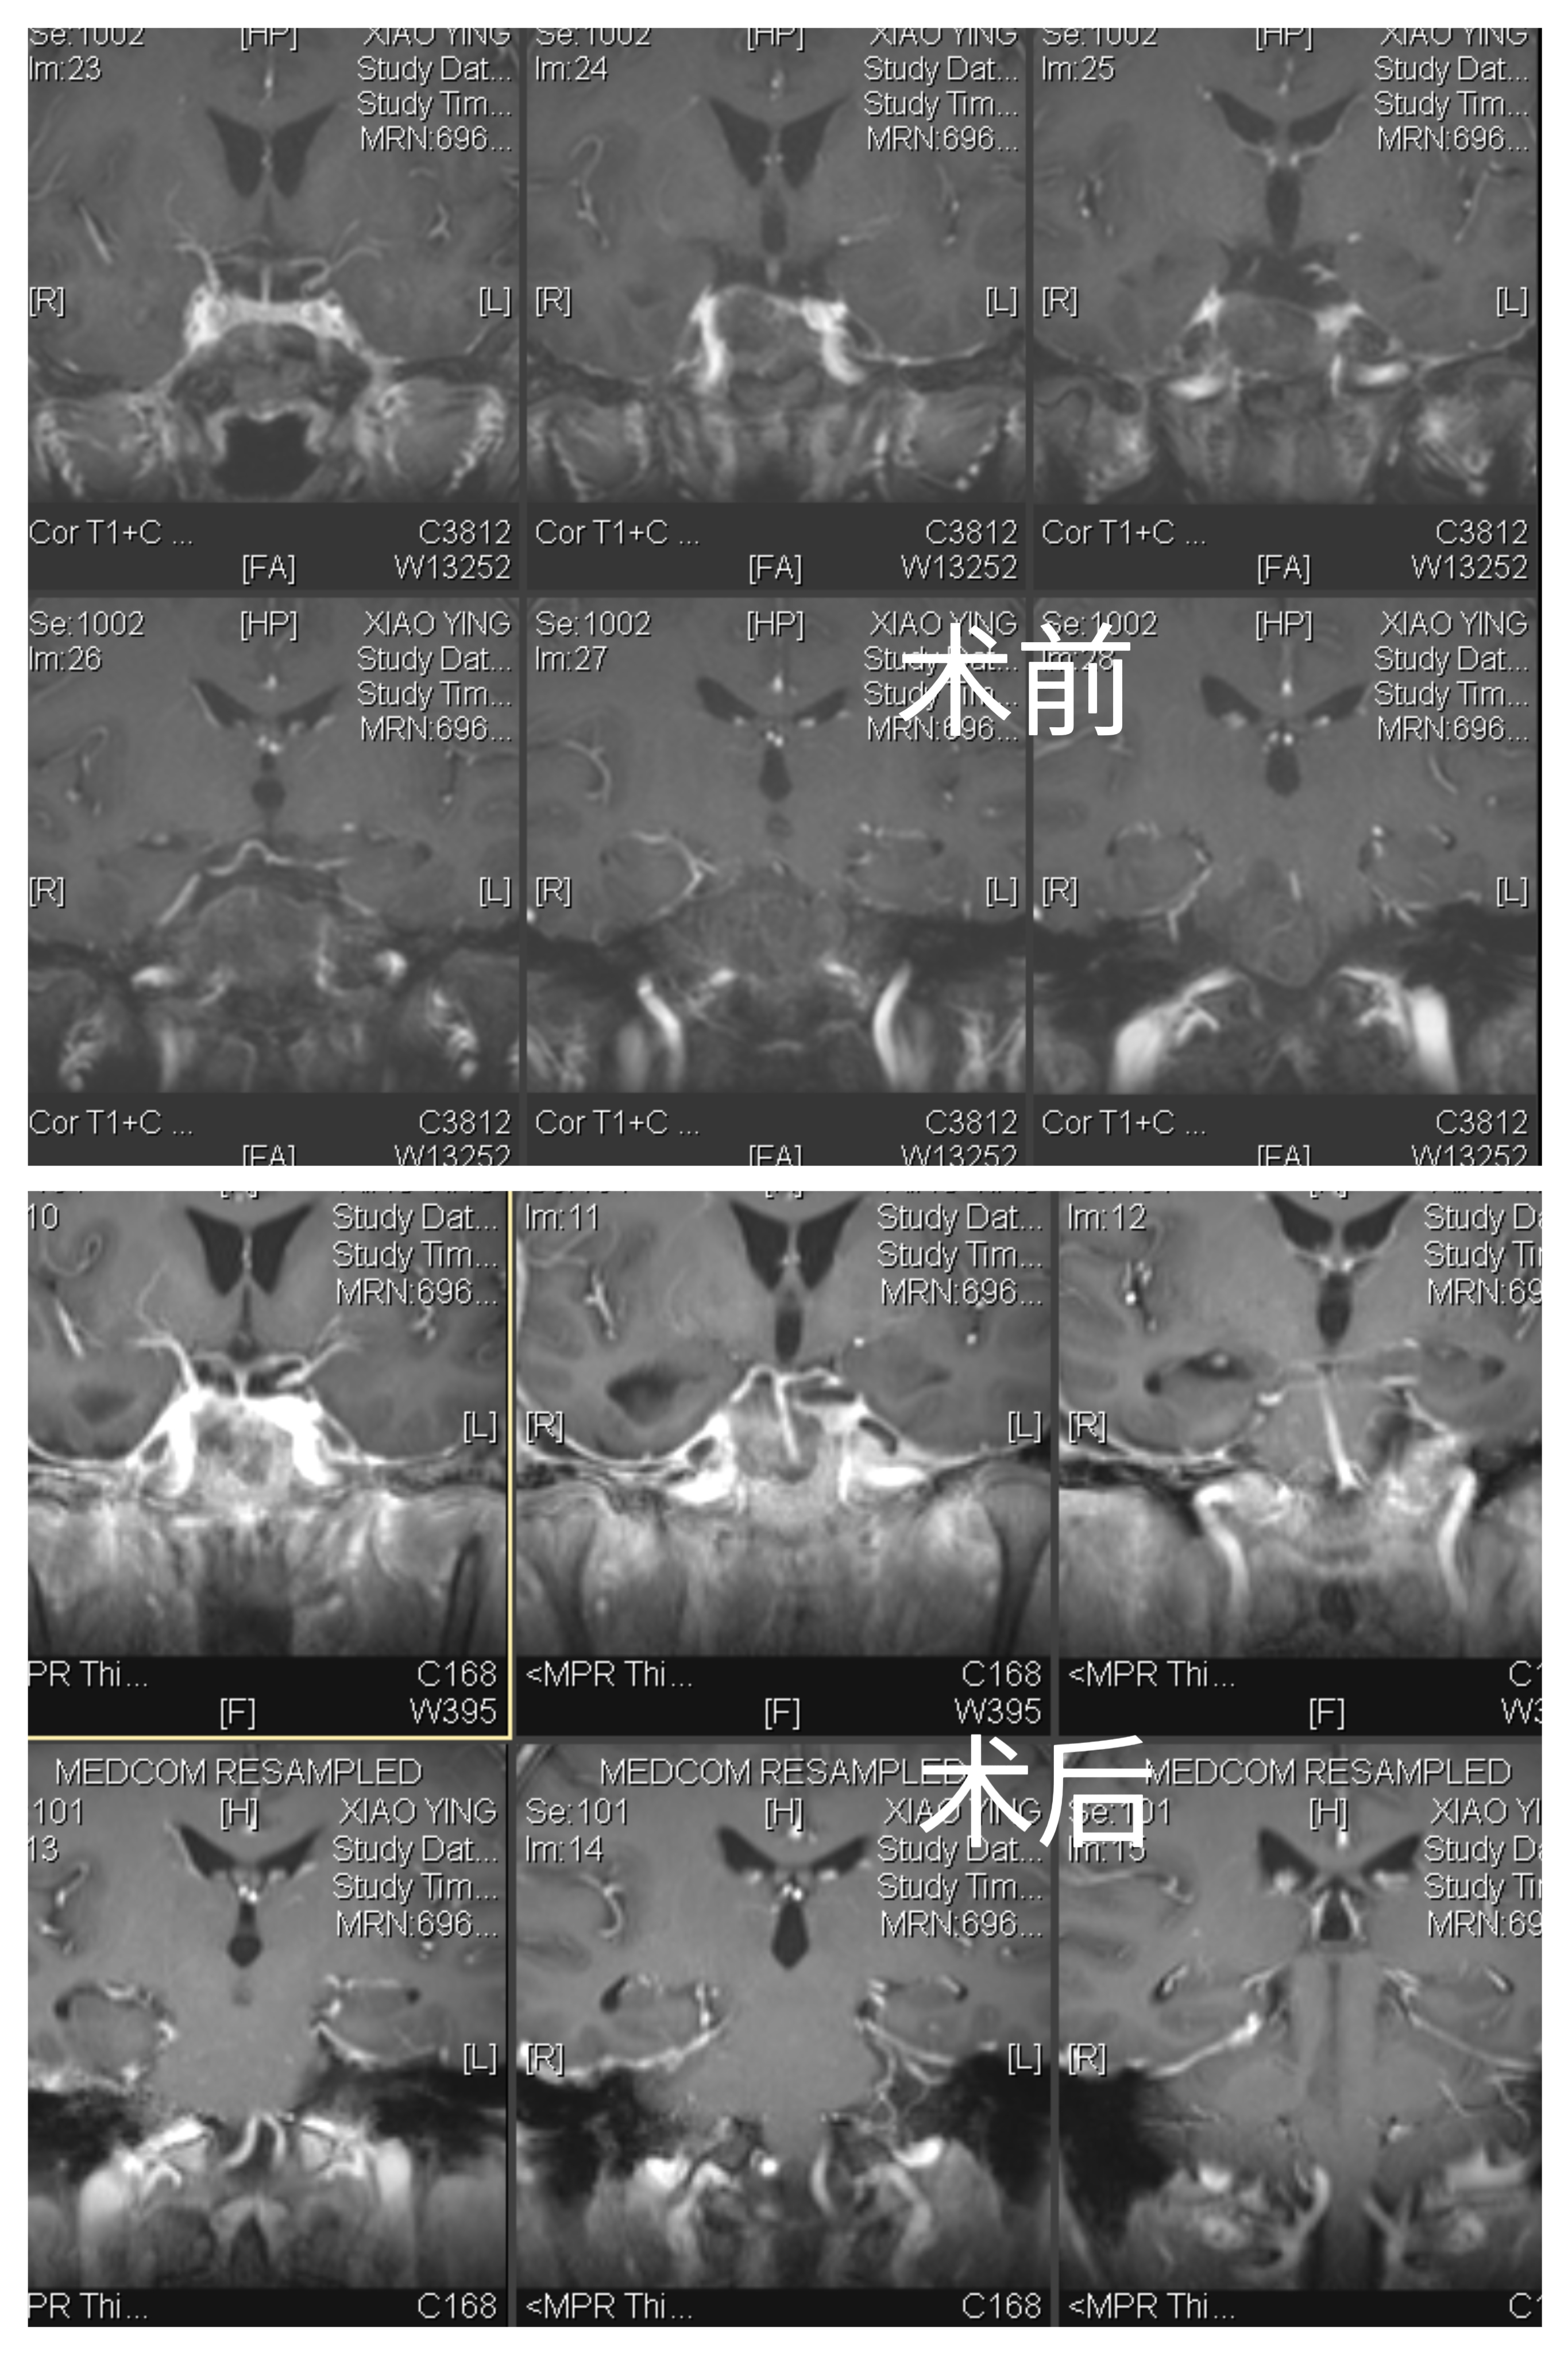

女性患者,56岁,因“视物重影4月”于2023-07-11入院。

入院诊断:斜坡脊索瘤

全麻成功后,病人仰卧位,头部向左侧偏转,右侧肩下垫枕。于右侧额颞部标记耳前颞下手术切口线。常规碘和酒精消毒,铺无菌单巾,沿切口线逐层切开头皮、帽状腱膜和颞肌,撑开皮肌瓣。止血后颅骨钻1孔,铣刀铣开取下骨瓣。

硬膜张力较高,色白,丝线悬吊骨窗硬脑膜止血。开放腰椎外引流,硬膜外抬起颞叶,予棘孔处电灼脑膜中动脉并切断。

魔钻磨除Kawase三角,见部分肿瘤位于硬膜外,肿瘤灰黑色,质软,血供丰富,使用环形刮匙和取瘤镊分块切除肿瘤,肿瘤包膜与颅底神经黏连严重,予以部分切除。弧形剪开颞部硬脑膜,脑组织博动正常。抬起颞叶,于滑车神后方切开小脑幕,电灼岩上窦,即见肿瘤,肿瘤灰红色,质软,血供一般,与双侧IV、V、VI、I、V颅神经及基底动脉粘连。显微镜下次全切除,部分肿瘤外包膜与上述神经血管黏连严重予以保留。创面电凝和速即纱压迫彻底止血。清点器械物品无误,硬膜下置引流管1 根,使用人工硬膜缝合硬脑膜,可吸收硬膜封合胶予以加固,复位并固定骨瓣,头皮和颞肌止血后,逐层缝合颞肌、帽状腱膜和头皮。